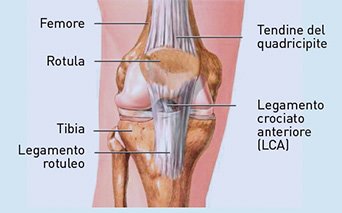

Lesioni legamentose e muscolo-tendinee (LMT)

Il collagene costituisce circa l’80% del peso secco (DW) di tendini, legamenti, tessuto connettivo associato ai muscoli. La sua perdita favorisce l’insorgere di tendinopatie, distorsioni e lesioni muscolari.